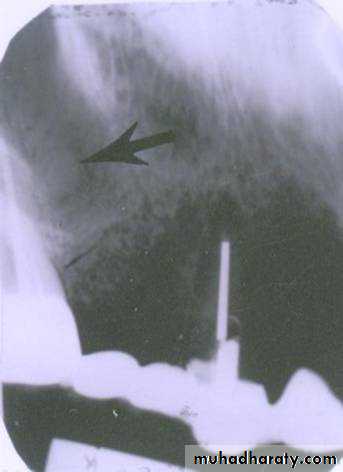

FISSURE BUR

FOREIGN BODYWATERS VIEW(Occipitomental )

LATERAL VIEWLateral oblique